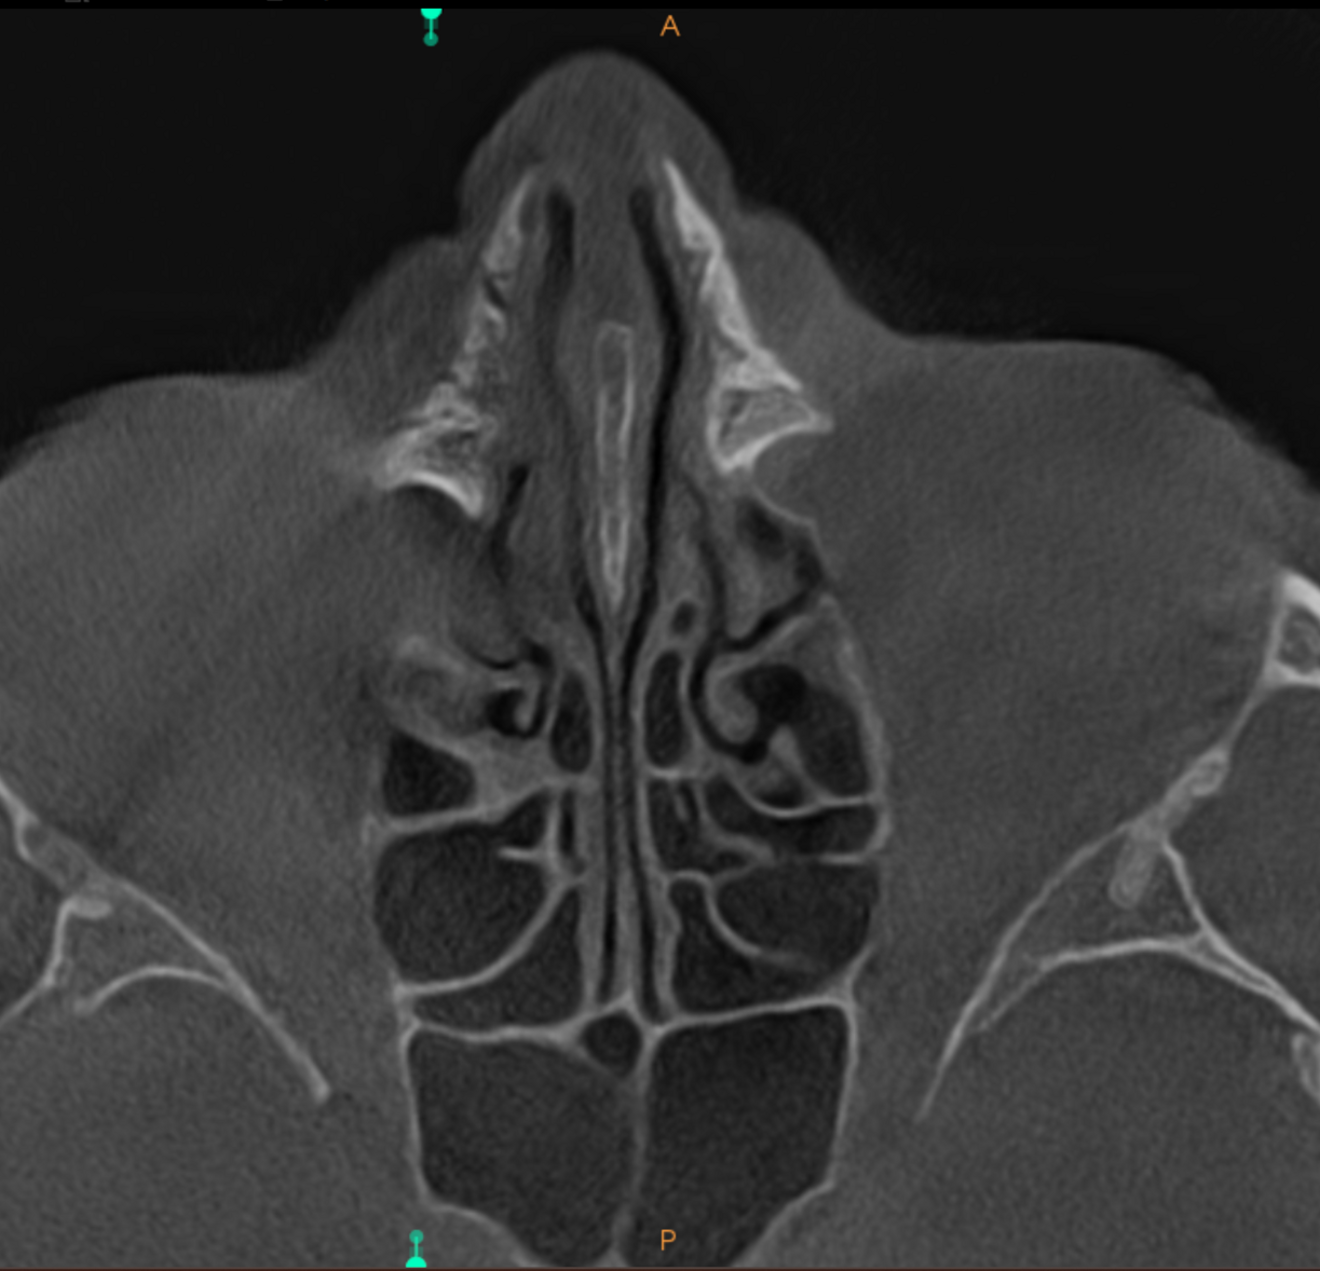

Fig. 3: Large-volume CBCT scan, frontal cross-section showing increased radiopacity in the paranasal sinus area.

The extent of the inflammation was shocking (Figs. 2a & b). Not only the maxillary sinus (Fig. 3) but the ethmoid and sphenoid sinuses too were involved, and the inflammation had spread towards the right cavernous sinus as well (Fig. 4). At this point, extraction may have been the first choice for most dental clinicians, but we had to keep in mind that invasive treatment may have increased the risk of cavernous sinus thrombosis, a potentially avoidable possibility. There are very few circumstances under which a dental procedure can cause very severe or even lethal consequences, but this case approached such a situation.